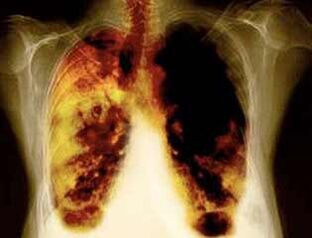

- Reducción del riesgo de desarrollar cáncer de pulmón y muchos otros tipos de cáncer.

- Reduciendo el riesgo de desarrollar ciertas enfermedades pulmonares (por ejemplo, enfermedad pulmonar obstructiva crónica).

- Después de 1-9 meses, la tos y la falta de aliento tienen lugar: los cilios (pelos pequeños) comienzan a tratar el moco normalmente, limpiando los pulmones y reduciendo el riesgo de infección.

- 10 años después del cese de fumar en un 40%, la probabilidad de cáncer de pulmón disminuye en un 40%.